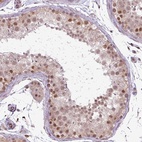

Immunohistochemical staining of human testis shows moderate nuclear positivity in cells in seminiferous ducts and Leydig cells.